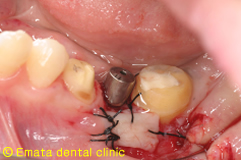

| インプラント手術。歯肉の移植も行いました。 | |

| 歯牙移植・インプラントのどちらが有利かは診査・診断をしっかりおこない適応症を見極めることです。 | |